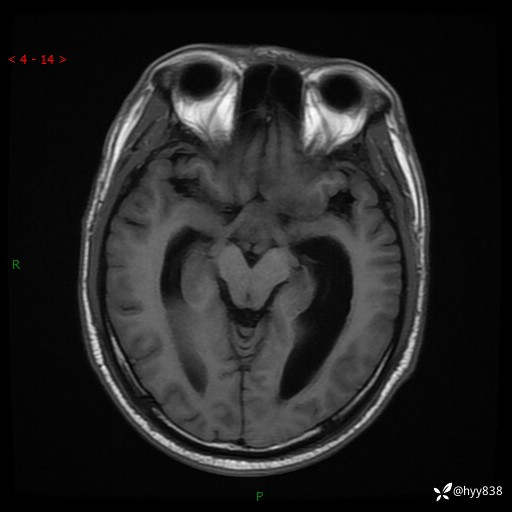

颅脑MRI平扫+增强